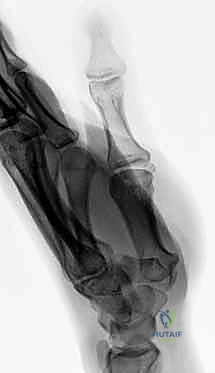

- العظم الكلابي (Hamate): يمتلك بروزاً عظمياً يُسمى "الخطاف". كسور هذا الخطاف شائعة بين الرياضيين (لاعبي التنس، الجولف، البيسبول) وتسبب ألماً مزمناً إذا لم تُشخص.

شاب رياضي (25 عاماً) سقط أثناء ممارسة كرة السلة وعانى من ألم مزمن في قاعدة اليد لمدة 3 أشهر، تم تشخيصه خطأً على أنه التواء. بعد زيارته لعيادة الدكتور هطيف، أظهرت الأشعة المقطعية الدقيقة كسراً في "خطاف العظم الكلابي" (Hamate hook fracture). تم إجراء عملية جراحية دقيقة لاستئصال الجزء المكسور الصغير الذي كان يضغط على الأوتار. بعد 6 أسابيع من التأهيل، عاد اللاعب لممارسة الرياضة بكامل كفاءته.